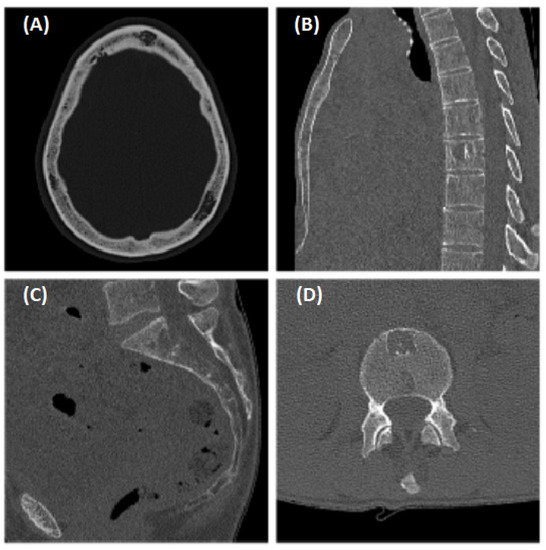

2. Case Description